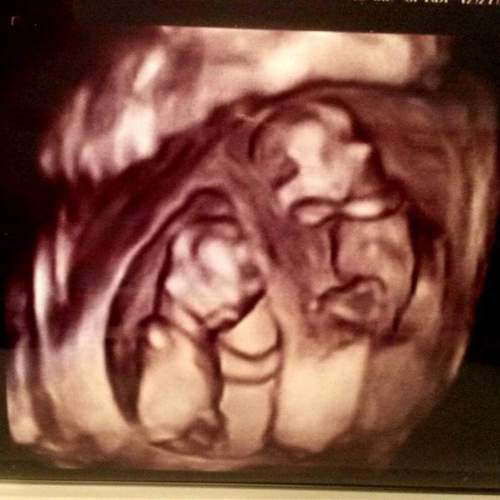

Ultrasound Photos at 21 Weeks Pregnant With Twins